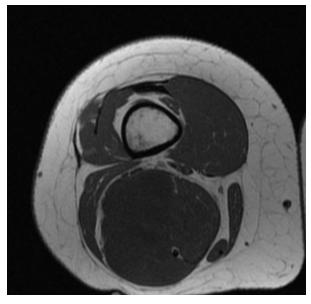

Radiographic imaging is used to help form a diagnosis of pleomorphic liposarcoma. These include X-Ray, MRI, CT and Bone Scans

An example of an MRI is shown.